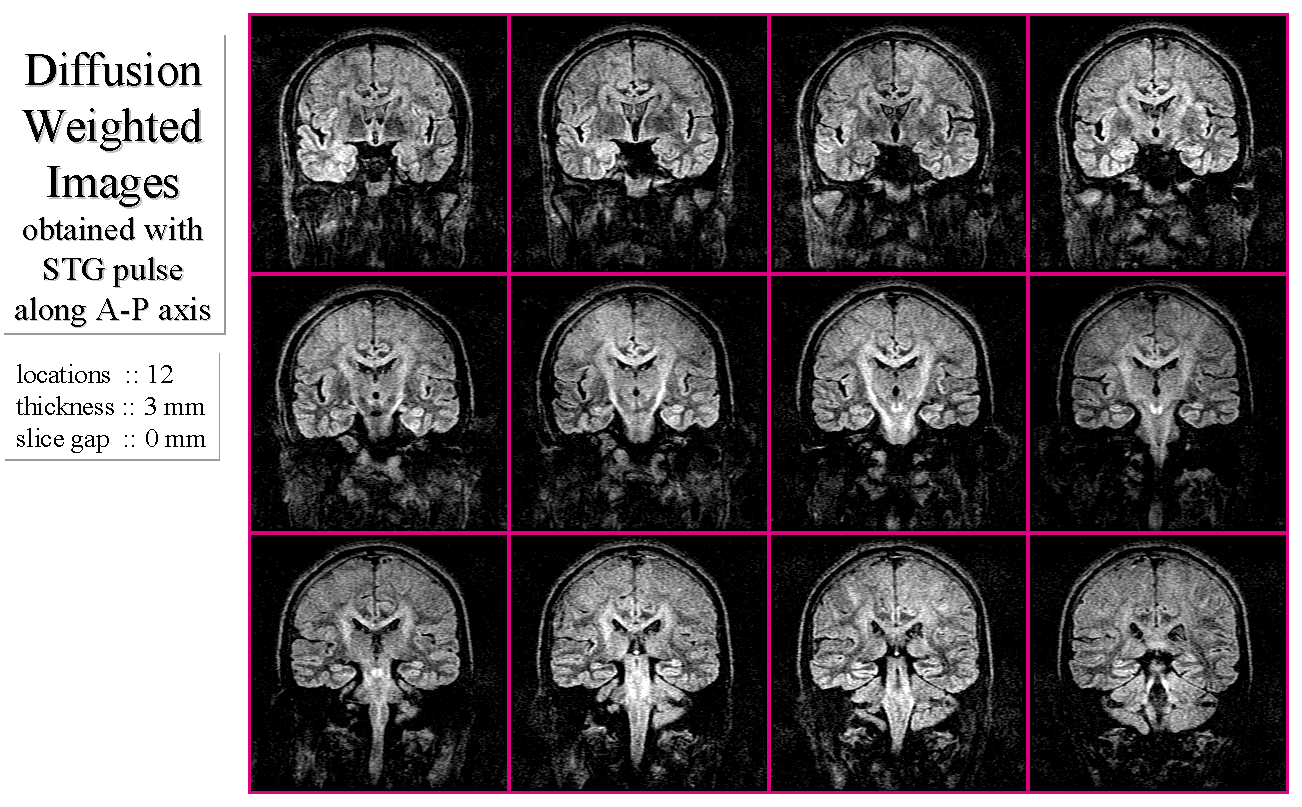

MRI装置の技術進歩は著しい。数年前まで高画質の取得が困難であると思われていた拡散強調撮像法は、EPIを可能とする装置によってモーションアーチファクトを最小限に抑えた画像の取得が可能となっている。また、撮像法として従来よりSEパルス系列にSTG(Stejskal-Tanner gradient)パルスを組み込んだ手法が一般的であったが、EPI装置の出現とともにSE-EPIパルス系列にSTGパルスを組み込んだ手法に移行しつつある。

図2にスピンエコー法の180度RFパルスの前後に拡散検出用のSTGパルスを加えたStejskal-Tannerパルス系列を示す。また、Stejskal-Tannerパルス系列と脳神経白質群の拡散異方性を利用した脳白質神経路の描出を検討する。Stejskal-Tannerパルス系列で撮像された画像の信号強度

は次式である。

図6

一連の拡散強調画像群